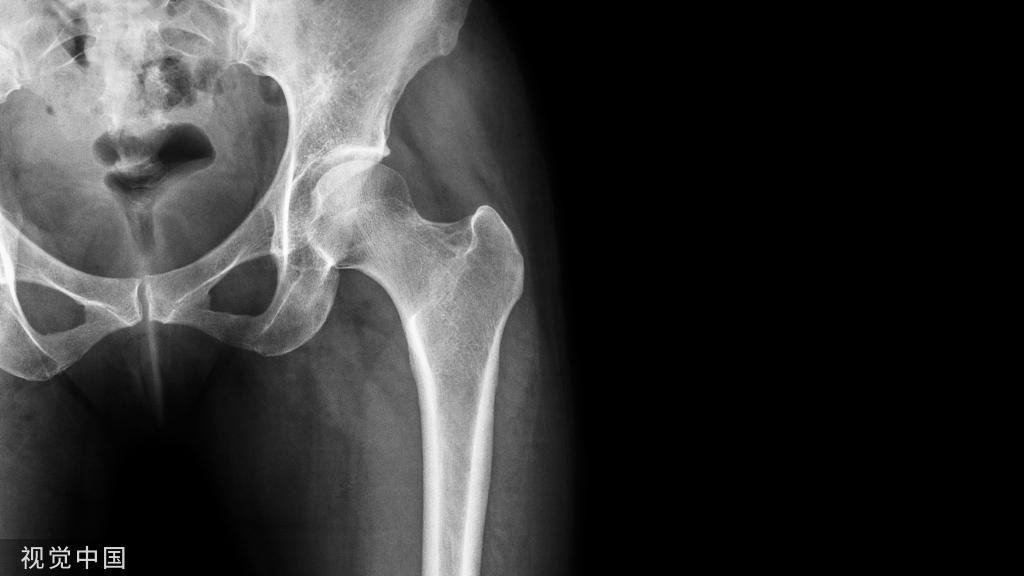

除了患者的症状及体征外,临床上腘窝囊肿的诊断通常还需要通过影像学检查来确定。X线检查通常无法显示囊肿,但可以排除其他病变。超声、CT和MRI可以帮助确定囊肿的位置、大小和形状,以及与周围组织的关系。

选择何种方式可依据术前核磁共振的检查情况决定。核磁共振显示腘窝囊肿与关节腔相通,腓肠肌间隔血管、神经的囊肿时建议的手术方式为前内外侧入路处理膝关节腔病变+单后内或双后内入路切除囊肿。如下图所示:

如下图所示,核磁共振显示腘窝囊肿与关节腔不相通,与血管、神经相邻的囊肿,可选择开放手术,降低神经、血管损伤的风险。